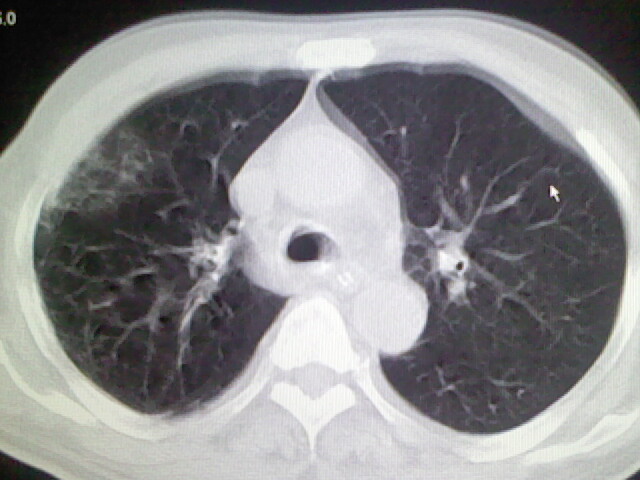

男,70岁,脑出血,长期卧床,左侧背部可触及肿块

背部没见到肿块呀,有感染灶。

考虑右肺及左肺下叶炎症。

右肺及左肺下叶炎症。

考虑右肺及左肺下叶慢性炎症。

肺部感染,背部筋膜增厚,考虑坠积性水肿或炎症